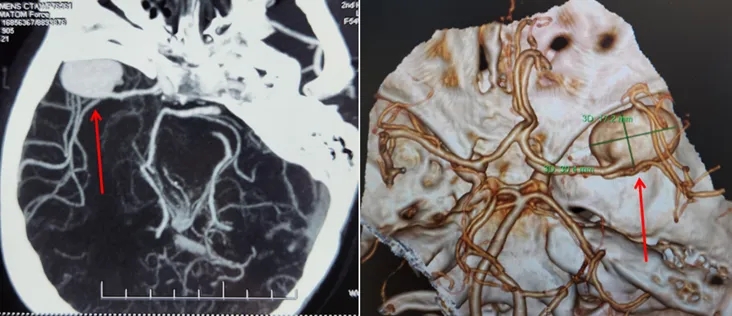

患者右颞部搏动性剧痛10天,遍访多家医院未果,慕名到我院神经外科五病区求医。张更申、吴建梁教授凭借丰富经验迅速为患者安排了头CTA检查,发现其右侧大脑中动脉有一枚直径达30mm的巨大动脉瘤,远超常规大小,已至破裂边缘,情势危急,决定立即手术,预防致命出血。

神经外科五病区迅速启动预案,紧急收治患者并进行脑血管造影等术前检查,精确诊断复杂动脉瘤位于右脑中动脉M1-2分叉,手术难度极高、风险巨大。

吴建梁教授团队经周密研讨,制定了精细入微的手术计划,术中精准剥离动脉瘤,同时运用高超显微外科技术,以桡动脉精准重建受损脑血管,恢复脑部血供。